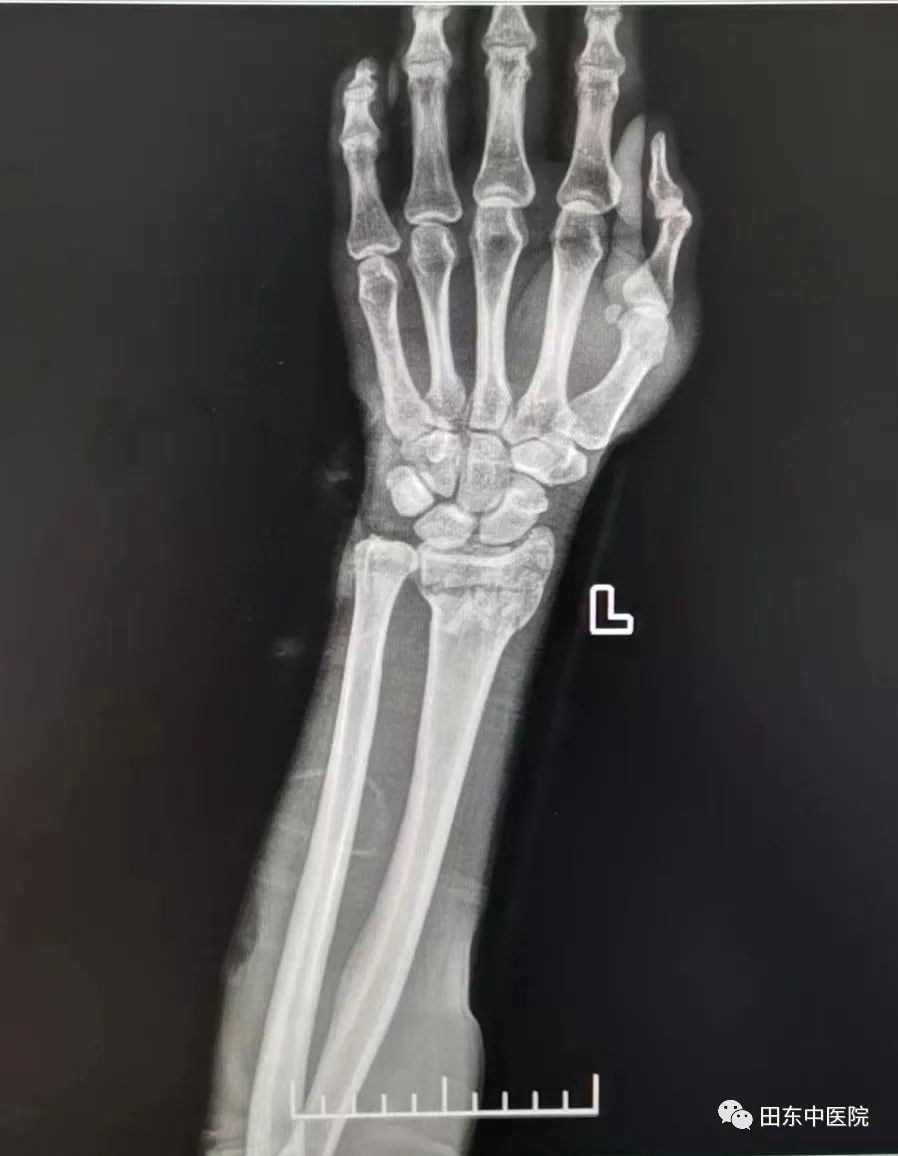

固定后经复查拍片显示:原左侧桡骨远端断端对位线尚可,左腕关节在位。农主任嘱咐患者注意手部皮肤颜色,观察末梢血液循环、感觉及运动情况,指导患者进行握拳伸掌功能锻炼,患肢前臂中立位固定于胸前或放置于身侧。

复位